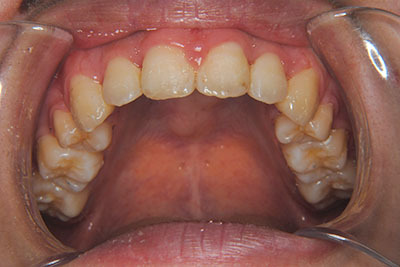

おとなの方でも矯正治療をあきらめないでください!

子供の頃に矯正治療を行う方が治療期間が短く済むというのは、確かですが、矯正治療は患者様の意識も重要です。

いくら歯が動き易くとも、本人がやる気でなければ効果は出ませんし、むし歯発生のリスクも高まります。おとなの方は顎の成長が終わっているため、治療の計画が立てやすいとも言えます。「もう大人だから…」とあきらめず、一度ご相談ください。